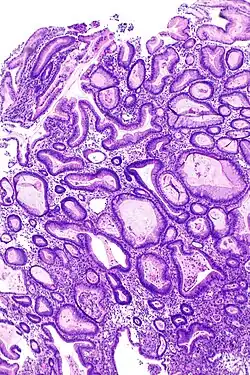

![]() Obraz hiperplazji fałdów błony śluzowe żołądka w przebiegu choroby Ménétriera. Warstwa mięśniowa błony to wygięta struktura widoczna w środku i na dole, obok miejsca uchwytu narzędzia | |

Typowy obraz mikroskopowy w chorobie Ménétriera obejmuje: 1. Rozrost dołeczkowy (łac. hyperplasia foveolaris; wydłużenie, kręty przebieg i torbielowate rozdęcie dołeczków żołądkowych ze wzrostem liczby komórek śluzowych oraz zmniejszeniem liczby komórek okładzinowych i głównych, pogrubienie blaszki mięśniowej błony śluzowej z wnikaniem pasm komórek mięśniowych gładkich w obręb blaszki właściwej); 2. Skąpy lub bardzo skąpy naciek zapalny. Ponieważ zmieniona śluzówka podatna jest na uszkodzenia, częste jest występowanie jej nadżerek będących przyczyną utraty krwi i, w konsekwencji, niedokrwistości. Zmiany takie stwierdzane są u wszystkich pacjentów w obrębie dna i trzonu żołądka, a u do 46% także w obrębie części odźwiernikowej[9].